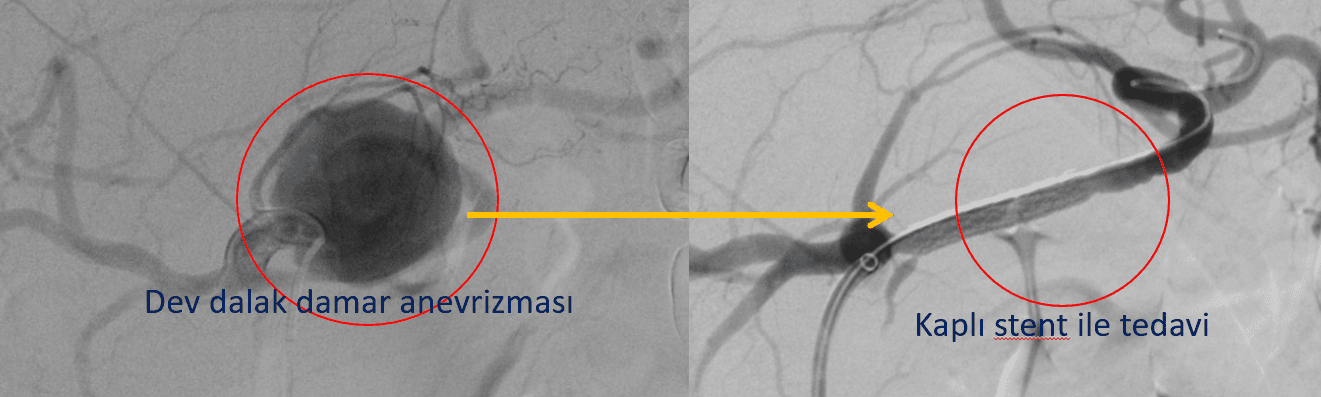

Ciddi kanama riski olan 4 cm çaplı splenik arter (dalak damarı) anevrizması kaplı stent ile sistem dışı bırakıldı. İşlem ameliyatsız, anjiyoda yapıldı ve anevrizmanın tamamen etkisiz hale getirilmesi sadece 27 dk sürdü.